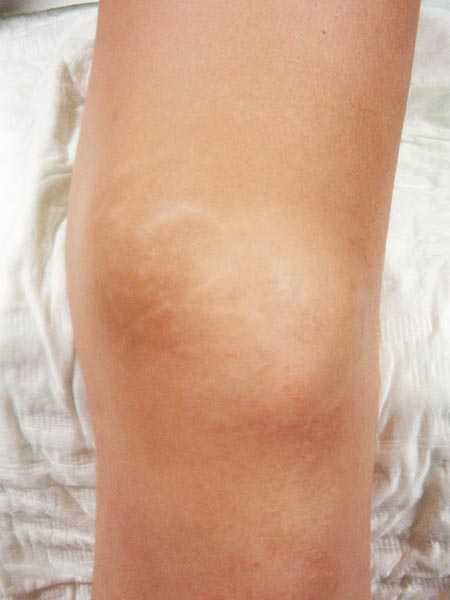

13-year-old female patient with recurrent painful swelling at the medial distal left thigh. Condition after surgical exploration, which was aborted due to severe bleeding. Histologically a "hemangioma" was diagnosed. However, this diagnosis does not correspond to the biological behavior of the lesion. Postoperatively no improvement of the exercise-dependent pain.

The completely occluded venous malformation was successfully resected after successful embolization and sclerotherapy following complete occlusion. The patient has thus far been asymptomatic (3 years, 4 months).